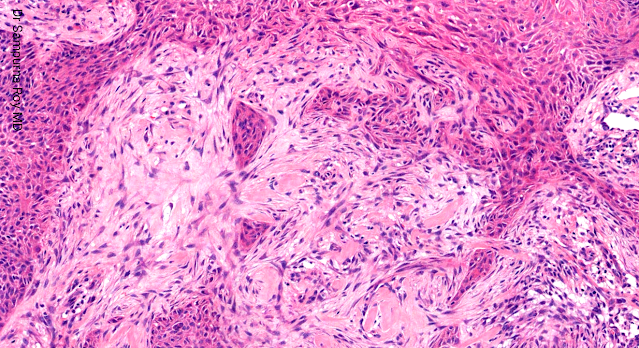

Dermatopathology Case 191 Get link Facebook X Pinterest Email Other Apps April 07, 2022 A 57-year-old man presented with a small papule on left side of the face. Answer Get link Facebook X Pinterest Email Other Apps Comments